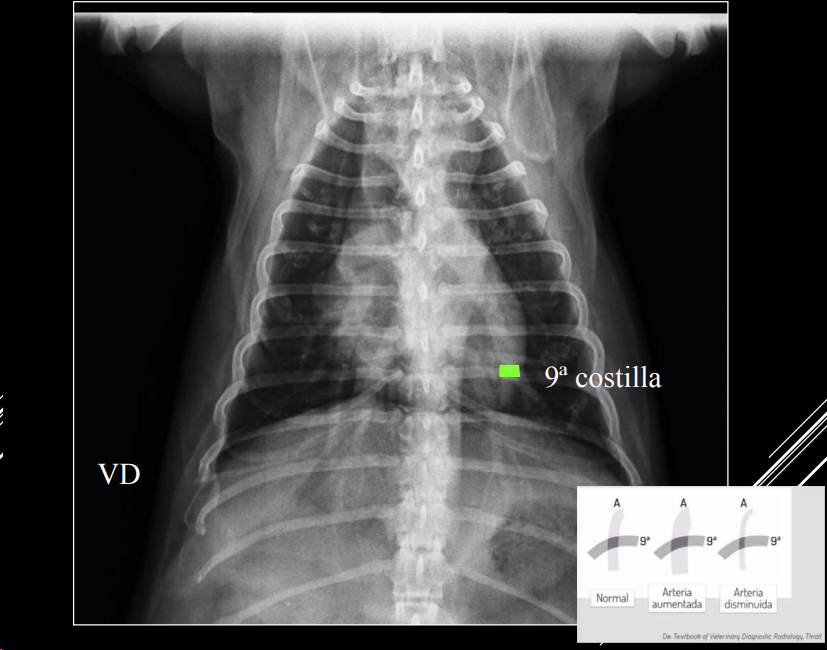

PATRÓN VASCULAR

- Cambios en tamaño, densidad o forma de vasos.

- Arteria y vena lobulares craneales del mismo tamaño.

- Comparación: grosor ≈ 4ª costilla (LL) o 9ª costilla (VD).

- Hipervascular o hipovascular.

- Posible mineralización (uremia, filariosis).

- Tortuosidad o cortes bruscos en arterias pulmonares → filariosis.